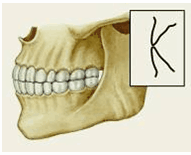

Различают несколько вариантов нормального П. (ортогнатический, прогенический, прямой, бипрогнатический). Они характеризуются смыканием зубных рядов на всем протяжении и отличаются друг от друга лишь особенностями смыкания функционально ориентированных групп зубов, в частности передних. Эталонным принято считать ортогнатический прикус (рис. 5, а), при котором верхний зубной ряд на всем протяжении перекрывает нижний, а во фронтальном участке верхние резцы перекрывают нижние не более чем на 1

Рис. 5а). Схематическое изображение челюстей при основных разновидностях нормального прикуса (вид сбоку): ортогнатический прикус.

Рис. 5б). Схематическое изображение челюстей при основных разновидностях нормального прикуса (вид сбоку): прогенический прикус.

Рис. 5в). Схематическое изображение челюстей при основных разновидностях нормального прикуса (вид сбоку): прямой прикус.

Рис. 5г). Схематическое изображение челюстей при основных разновидностях нормального прикуса (вид сбоку): бипрогнатический прикус.